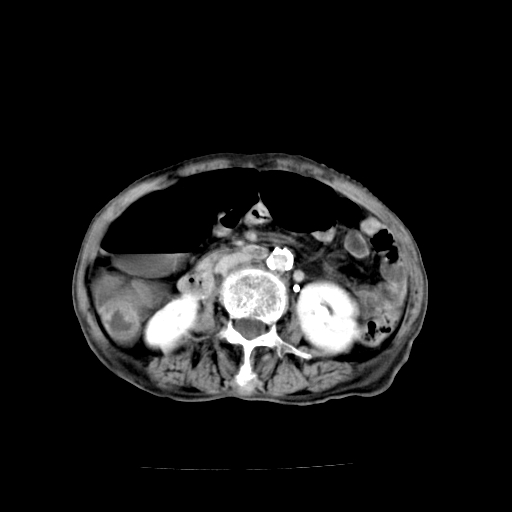

1)不排除胃窦癌;建议行胃镜检查。 2)局灶性脂肪肝。腹水。

考虑:胃窦ca,腹水,脂肪肝

1)胃窦壁厚,考虑胃窦癌?建议行胃镜检查。 2)局灶性脂肪肝。